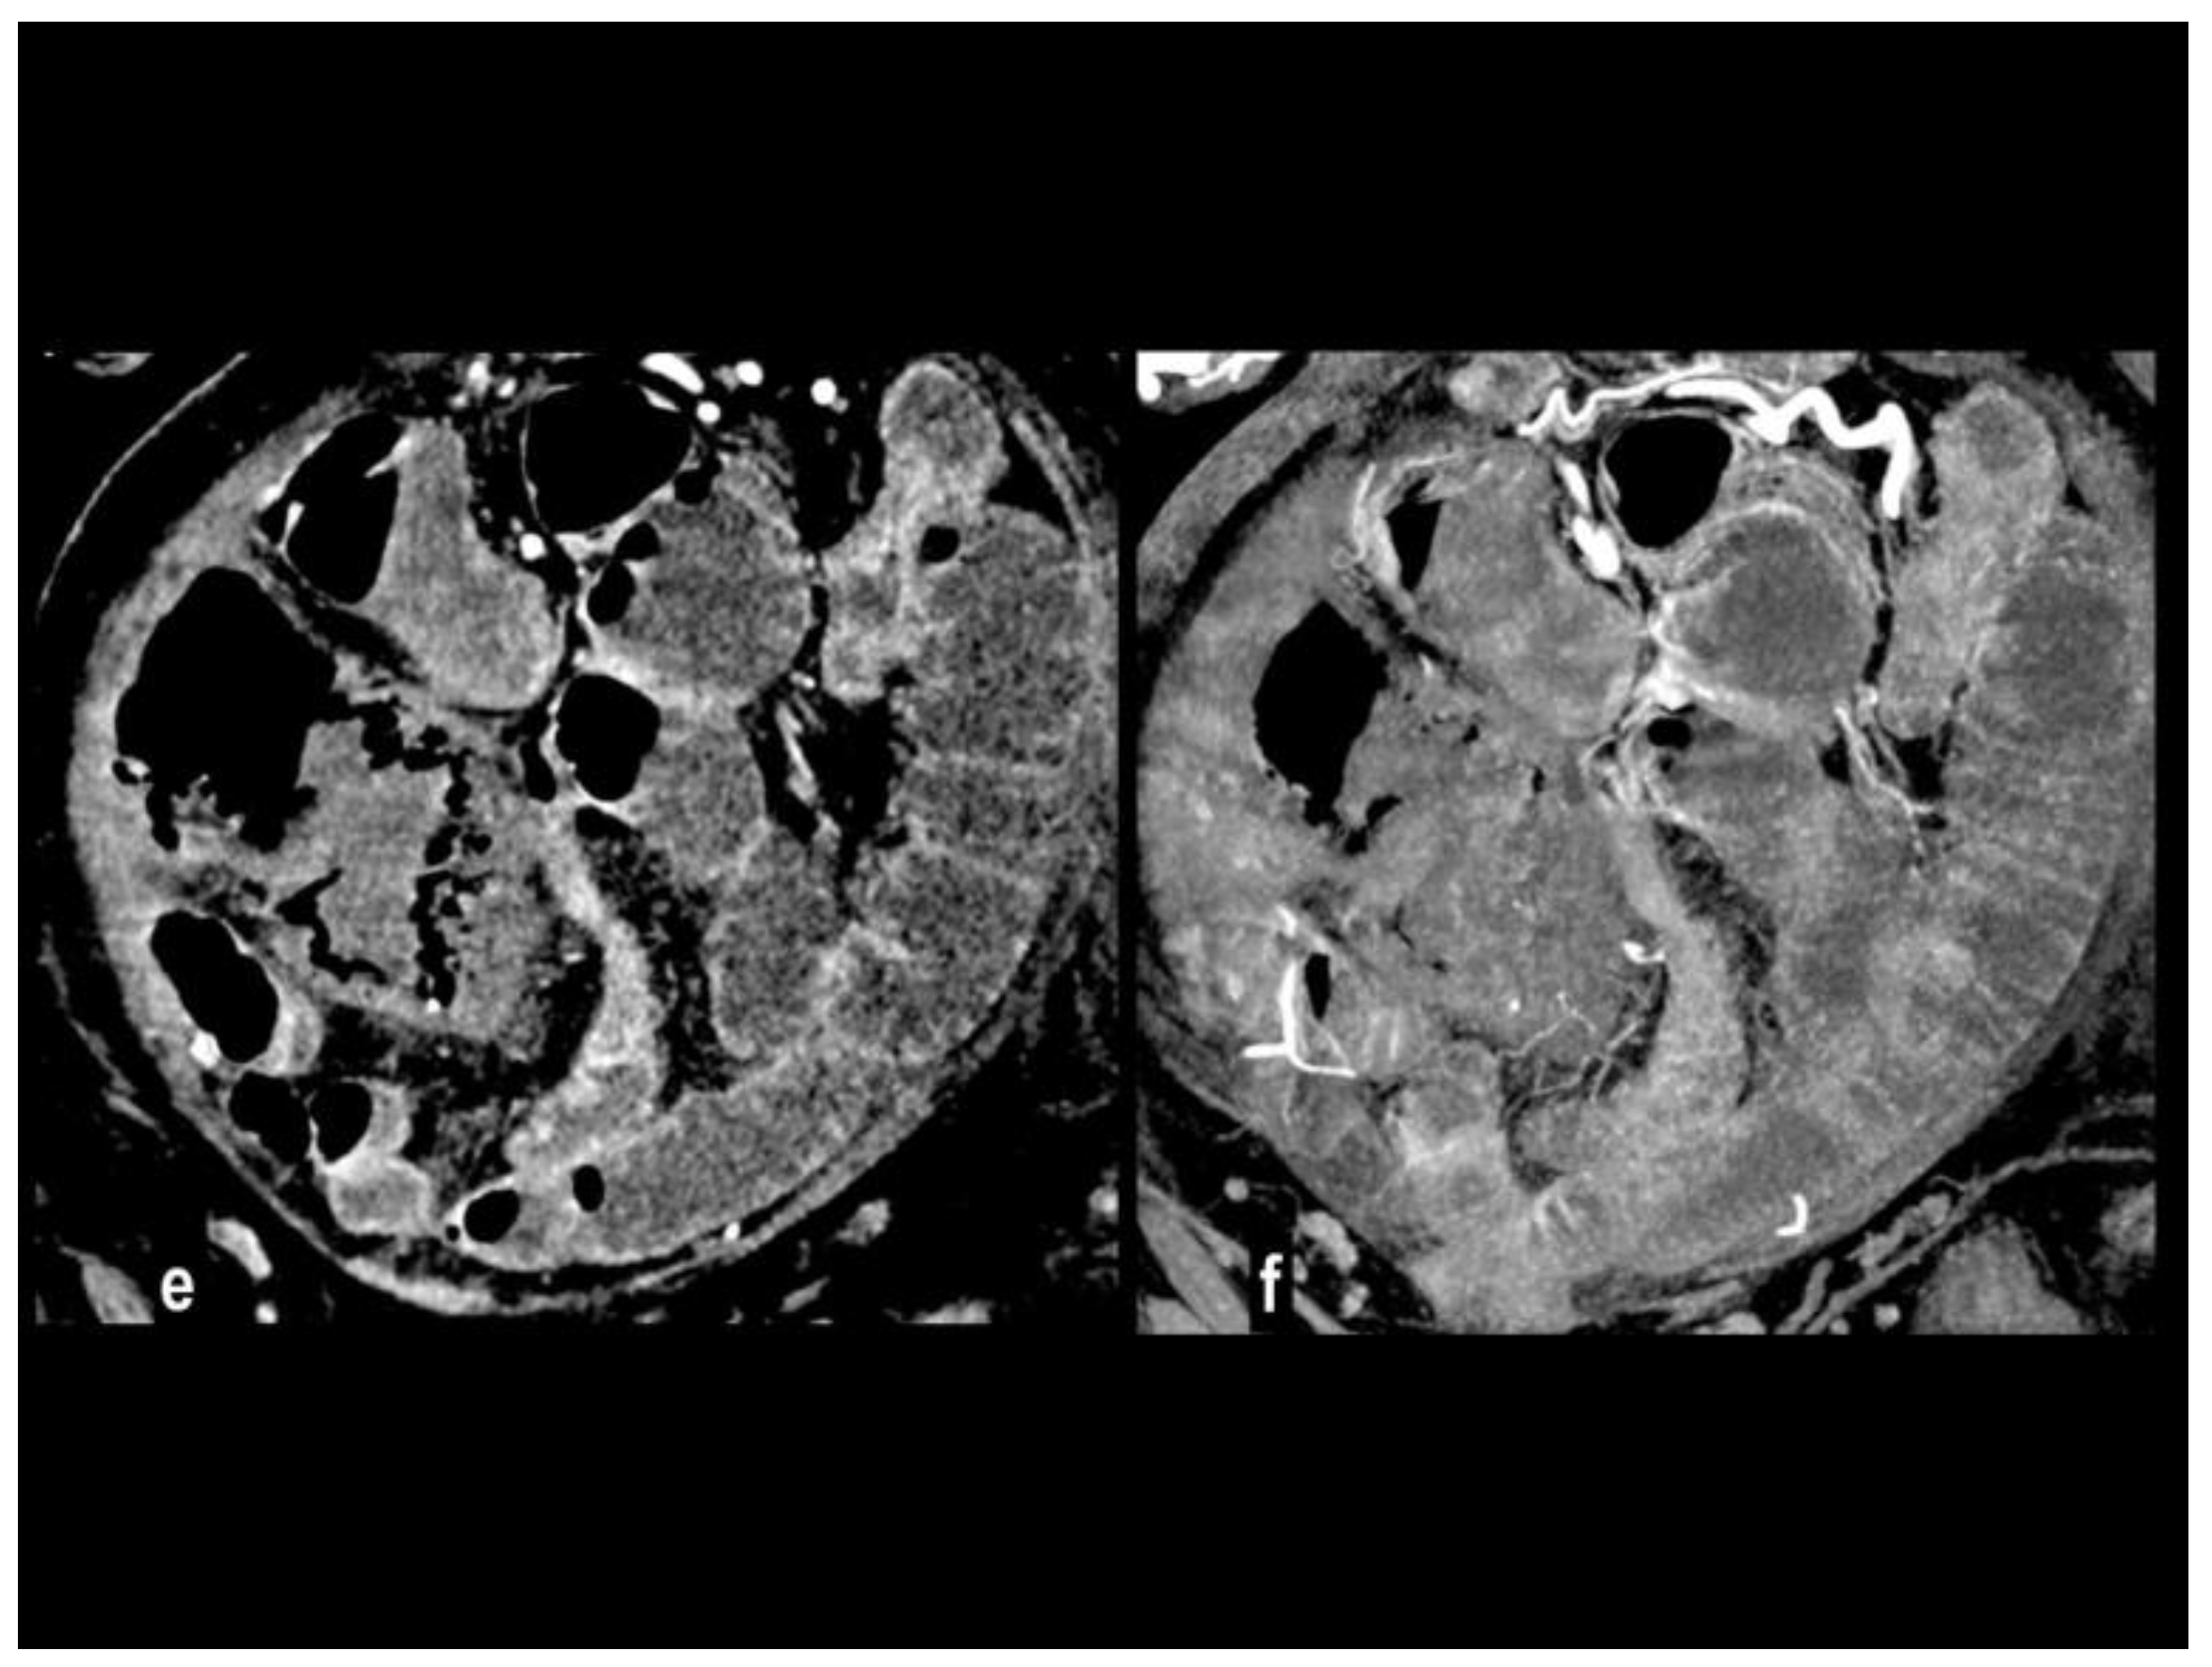

Figure 5. SMA dissection in a 42-year-old woman. MIP arterial images (Figure 5a-b) showed segmentary false lumen thrombosis in the proximal convex side of SMA, with lumen narrowing (arrow). The vessel caliber had increased (Figure 5c, oval). Distally the intimal flap continued in a complete vessel thrombosis (arrowhead), determining bowel ischemia with hypoenhancing paper-thin bowel walls (Figure 5d). Proximal false lumen thrombosis (arrow) and intimal flap (arrowhead) were also well depicted at ultrasound examination performed before MDCT (Figure 5e-f). The patient underwent surgical resection of necrotic loops.

Preprints 106216 g005aPreprints 106216 g005b